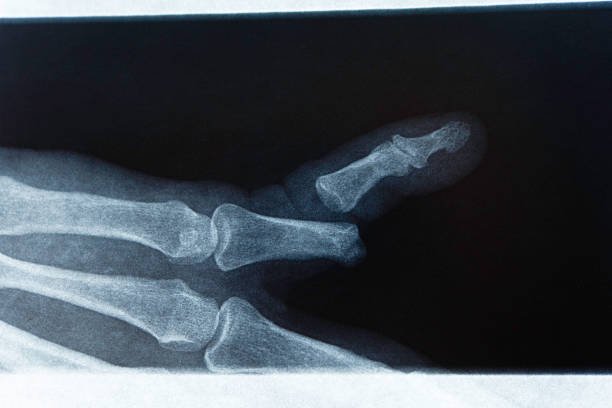

Symptoms of a broken finger: What Your Deformed Finger Might Indicate

A summary of symptoms indicating a broken finger or thumb

If you fracture your finger, pain is typically the initial symptom you’ll experience. Your finger might also appear deformed or misaligned. Additional symptoms of a broken finger might include:

Your doctor will then order an X-ray of your finger or hand to confirm a fracture and exclude other issues, such as a sprain in your finger or thumb.